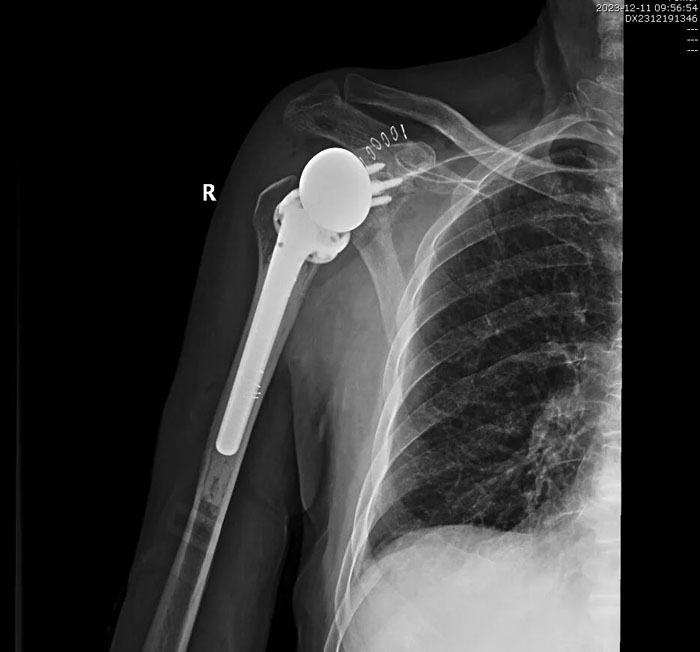

手術(shù)歷時2個小時順利完成,術(shù)后患者恢復(fù)良好,無并發(fā)癥發(fā)生,右肩關(guān)節(jié)功能明顯改善,患者對手術(shù)療效滿意。目前,患者已好轉(zhuǎn)出院,居家進(jìn)行功能康復(fù)鍛煉中。

術(shù)后